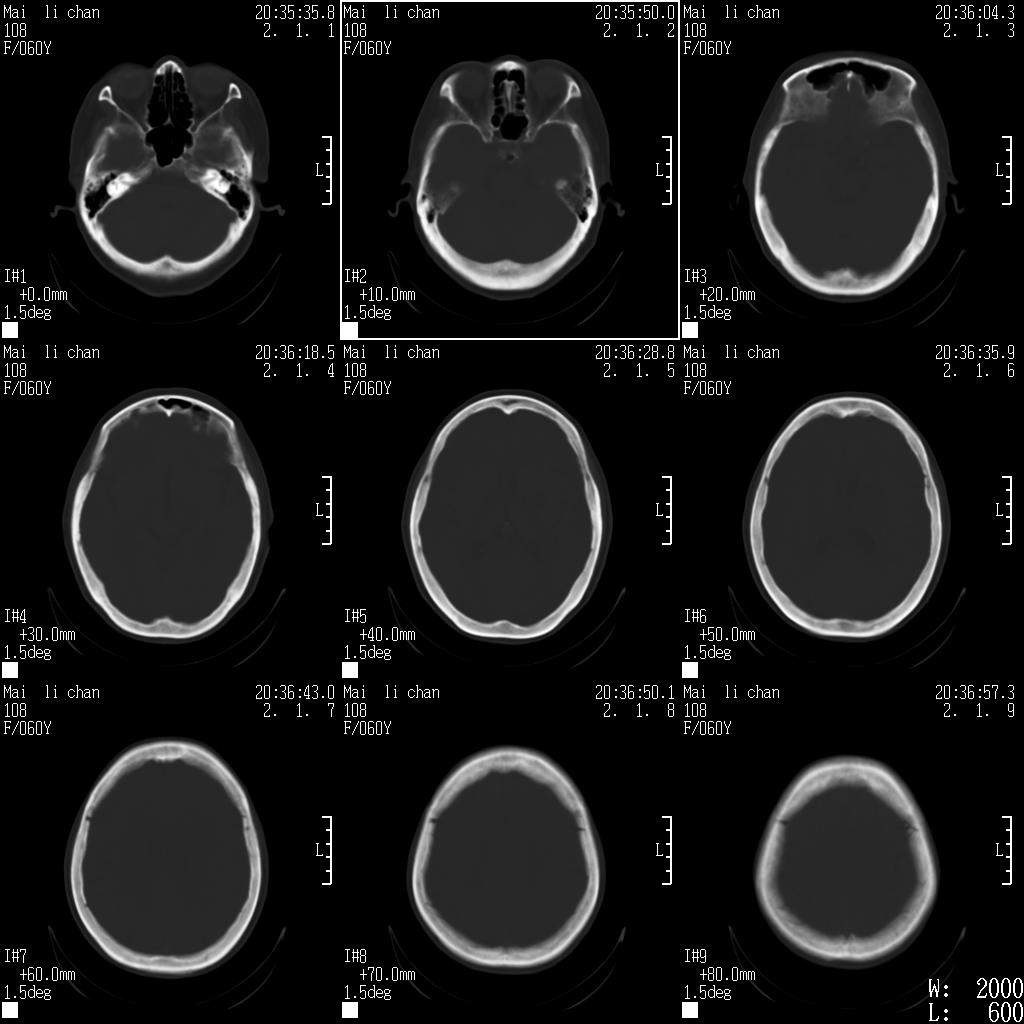

女性,60岁,右手无力一天

脑梗塞?并皮层下动脉硬化性脑病?还需要考虑什么?请大家指导,先谢了。

结合临床考虑梗塞,但看图片又不太像,面积太大,上下层面太少、

1.病人60岁,右手无力一天。

2.左侧基底节区可见片状低密度病灶。

意见考虑脑梗塞。

建议测量ct值及病灶大小